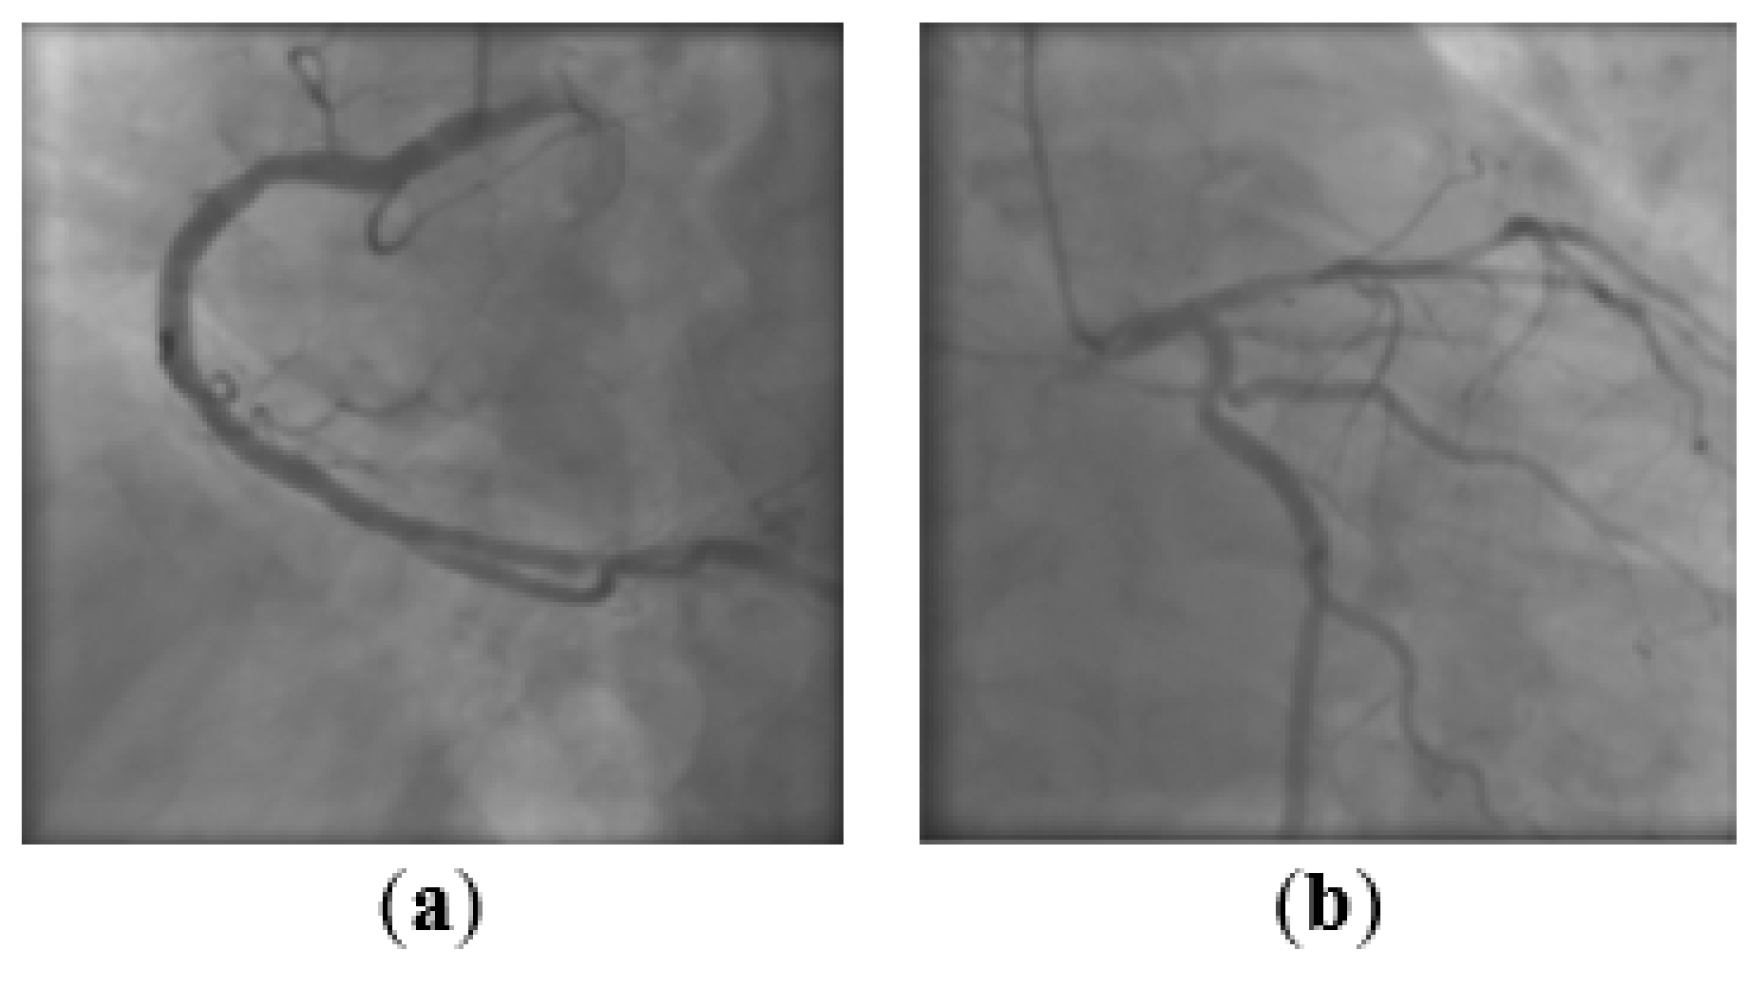

The task is to train a binary classifier to distinguish between RCA and LCA views in angiographic frames. Figure 7 depicts one sample of each category. The dataset contains 3280 coronary angiographies, balanced between the two classes. A subset of 600 images is used for validation, and another subset of 700 images is retained for evaluation purposes. The rest of the 1980 angiographic frames are used for training. Augmentation techniques such as shifting, flipping, zooming and rotation are applied. The original size of the frames is 512 × 512 pixels, but experiments with different input shapes have shown that a size of 128 × 128 ensures almost no loss in classification performance with a lower computational time. The pixels values are normalized through min-max scaling in the [0, 1] range.

Figure 7.

RCA—right coronary artery (a) and LCA—left coronary artery (b).